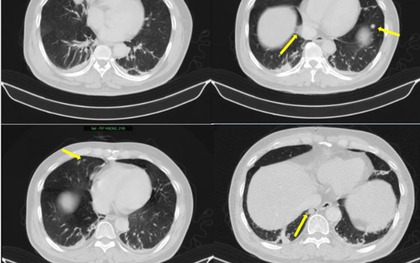

Một người bệnh 64 tuổi đồng thời mắc hai bệnh ung thư riêng biệt, một ở bàng quang, một ở ống mật chủ. Đáng nói, ông chỉ có 2 triệu chứng.